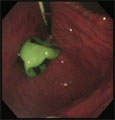

胃内のゴムボール

経過:一般状態は良好。全身麻酔下胃内視鏡検査にてただちに緑色のサッカーボールの模様のつぶれたゴムボール(異物)を確認できた。数十分奮闘し、最も大きな内視鏡処置具(異物をはさむ道具)でも取り出せなかった。内視鏡処置を断念し、検査後、食塩水投与で吐かせてみたが、結局それでも吐き出せなかった。特殊な器具を使って再度内視鏡処置を行うことや胃切開術を提案したが、飼い主様は無処置で様子を観察されることを希望した。